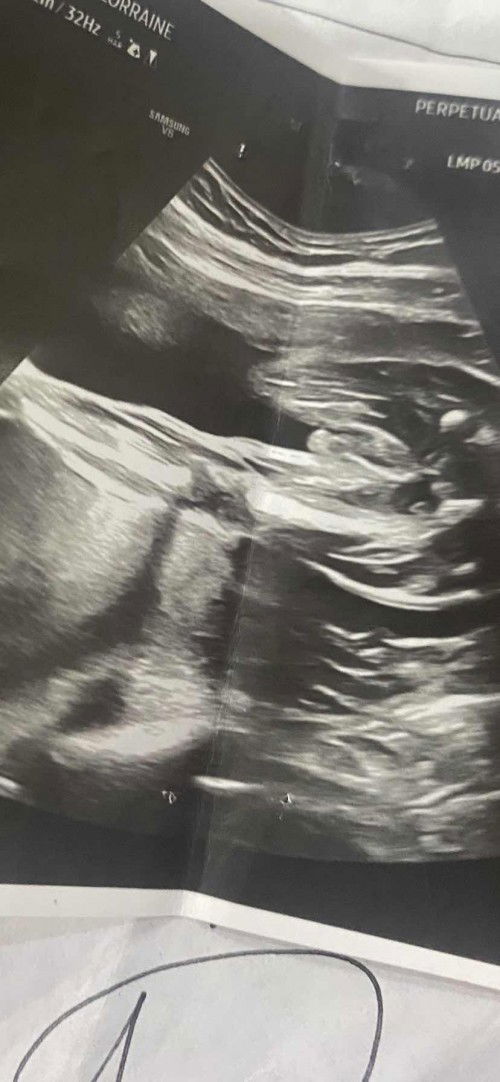

Ultrasound result

Hi mga mommies! Question lang po, if 90% na po ba ang nakalagay sa ultrasound, sure na po ba yun? Wala na bang pag asang mabago yun? 90% male po kasi yung akin and sana po sure na po talaga hehe. Yan po yung result ng ultrasound, yun po ba yung putoytoy ni baby? 😅